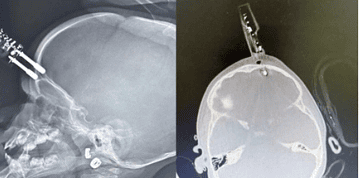

2º guia gazeta Carregador perfura crânio de criança de 1 ano após queda em casa por A Gazeta do Acre 16/01/2026